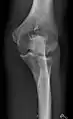

AP and lateral elbow X-ray

• Elbow - AP and Lateral. Radial head projections available on request

• Knee - AP and Lateral. Intra Condular projections on request